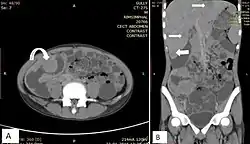

Diagram showing common sites where lymphoma spreads

After a diagnosis and before treatment, a cancer is staged. This refers to determining if the cancer has spread, and if so, whether locally or to distant sites. Staging is reported as a grade between I (confined) and IV (spread). The stage of a lymphoma helps predict a patient's prognosis and is used to help select the appropriate therapy.[43]

The Ann Arbor staging system is routinely used for staging of both HL and NHL. In this staging system, I represents localized disease contained within a lymph node group, II represents the presence of lymphoma in two or more lymph nodes groups, III represents spread of the lymphoma to lymph nodes groups on both sides of the diaphragm, and IV indicates spread to tissue outside the lymphatic system. Different suffixes imply involvement of different organs, for example S for the spleen and H for the liver. Extra-lymphatic involvement is expressed with the letter E. In addition, the presence of B symptoms (one or more of the following: unintentional loss of 10% body weight in the last 6 months, night sweats, or persistent fever of 38 °C or more) or their absence is expressed with B or A, respectively.[44]

CT scan or PET scan imaging modalities are used to stage a cancer. PET scanning is advised for fluorodeoxyglucose-avid lymphomas, such as Hodgkin lymphoma, as a staging tool that can even replace bone marrow biopsy. For other lymphomas, CT scanning is recommended for staging.[43]